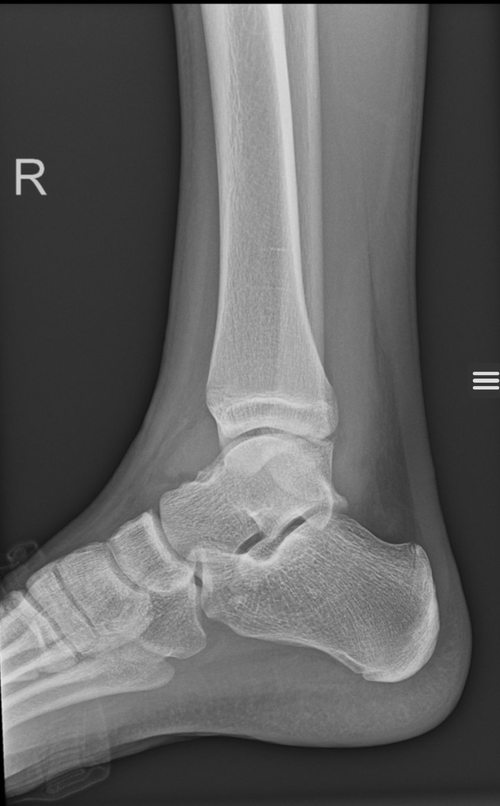

I got an x-ray from my feet can someone tell me how long my growth plates are going to be open